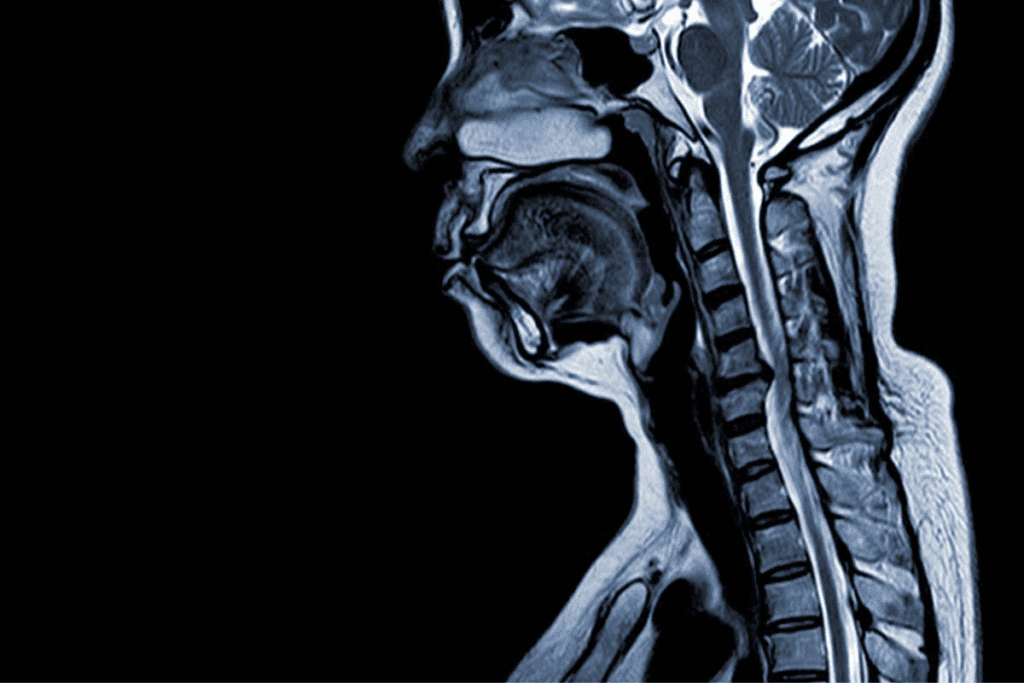

Imaging Studies (MRI, CT, X-rays)

Imaging is vital for confirming the diagnosis. MRI (Magnetic Resonance Imaging) is best for seeing soft tissues like discs and nerves. It’s the most accurate for L4-L5 disc bulges and nerve compression. CT (Computed Tomography) scans show bony details and can spot spinal stenosis or arthritis. X-rays check spinal alignment and bone health.